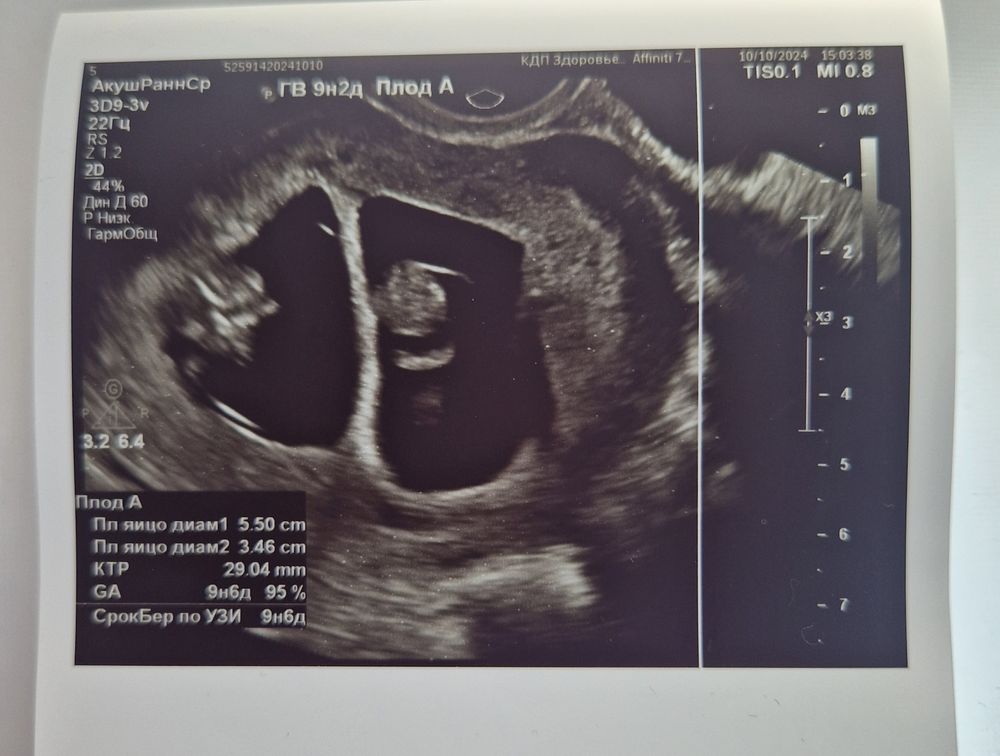

✏️48 дпп (9н 2д) - 10.10.24 Господи Спасибо за всё🙏🏻 Первый раз, когда я на УЗИ заревела, ну это просто не передать словами😍 Именно сегодня я услышала сердечки своих малышей, не просто мигающую точечку, именно звуком❤️ А как они мило шевелятся🥲 Один сразу начал, второй чуть позже когда начали его замерять🤗 Уже такие большие и главное не отстают друг от друга крепыши💪🏻

✏️УЗИ 48 дпп (9н 2д)

Диаметр первого ПЯ - 41 мм. ЖМ - 4,8 мм Хорион 10 мм.

Эмбрион КТР - 29 мм. СБ - 168 уд/мин.

Расположение по задней стенке, нижний полюс ПЯ

Диаметр второго ПЯ - 40 мм. ЖМ - 4,4 мм Хорион 10 мм.

Эмбрион КТР 29 мм. СБ - 166 уд/мин.

Расположение по передней стенке, дно.